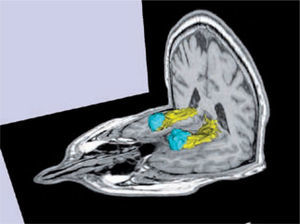

Volumetría y segmentación de los hipocampos (amarillo) y las amígdalas (celeste) de un sujeto normal.

Software Freesurfer (http://ftp.nmr.mgh.harvard.edu/).